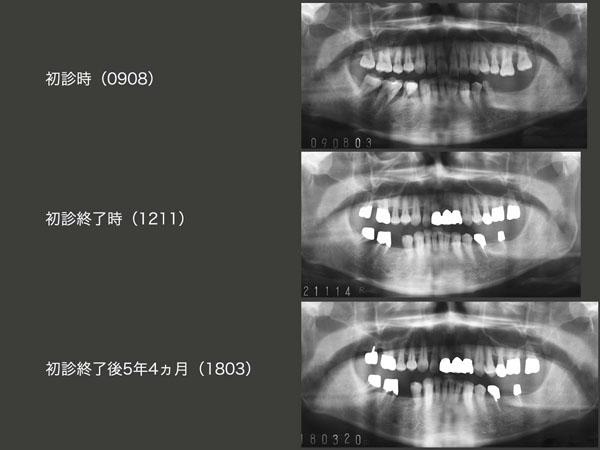

初診時,初診終了時,初診終了後5年4ヵ月のパノラマ写真の比較.この間,左下4レスト窩,右下6近心の根面にカリエスが生じ,治療している.かなり念入りにお手入れされているが,歯肉退縮に伴う露出根面のカリエスが心配である.歯周ポケットに関しては,右下7舌側中央が7mmに増加している.(担当:千葉奈保子)